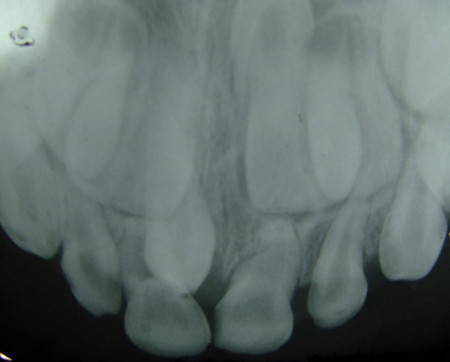

Hyperdontia adalah kondisi seseorang mempunyai jumlah gigi yang lebih banyak daripada jumlah yang normal. Gigi-gigi tambahan biasa disebut supernumary teeth tersebut bisa muncul di mana saja termasuk di langit-langit mulut.

Seorang anak laki laki berusia 9 tahun dari Cebu, Filipina menderita kelainan aneh yang terjadi pada giginya. Dimana anak yang bernama Johncris Carl Quirante tersebut, memiliki gigi yang berjumlah 300 buah di dalam mulutnya. Kejadian tersebut bermula pada saat berusia 2 tahu, anak laki laki itu telah memiliki gigi sebanyak 50 buah. Namun karena kondisi ekonomi, menyebabkan orangtuanya tidak bisa memberikan perawatan gigi kepada anak tersebut.

Ternyata anak laki laki tersebut menderita kelainan gigi yang disebut hyperdontia. Namun meskipun begitu, kelebihan gigi yang dimilikinya tidak membuat Johncris merasa terganggu saat melakukan aktivitasnya. Hal tersebut terbukti dari ia yang masih bisa bermain dan juga bersekolah bersama teman temannya. Bahkan, Johncris mampu menjadi siswa yang berprestasi di kelasnya.

Pernahkah Anda mendengar istilah hyperdontia? Istilah tersebut mengacu kepada kondisi seseorang, dimana memiliki jumlah gigi yang lebih banyak daripada jumlah normal. Gigi gigi tambahan yang tumbuh tersebut biasanya disebut supernumary teeth, yang mana bisa tumbuh dimana saja termasuk di langit langit mulut. Penderita kelainan tersebut, biasanya juga memiliki kondisi lain seperti bibir sumbing atau syndrom gardner.